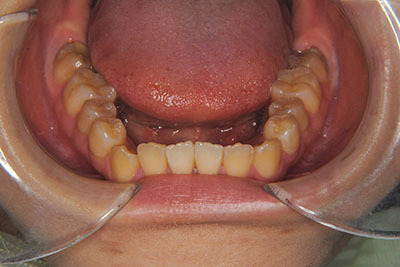

おとなの方でも矯正治療をあきらめないでください!

子供の頃に矯正治療を行う方が治療期間が短く済むというのは、確かですが、矯正治療は患者様の意識も重要です。

いくら歯が動き易くとも、本人がやる気でなければ効果は出ませんし、むし歯発生のリスクも高まります。おとなの方は顎の成長が終わっているため、治療の計画が立てやすいとも言えます。「もう大人だから…」とあきらめず、一度ご相談ください。